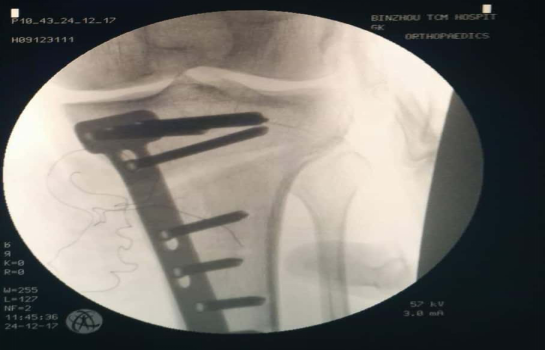

术后模拟负重位片显示:患者左膝内侧间隙恢复